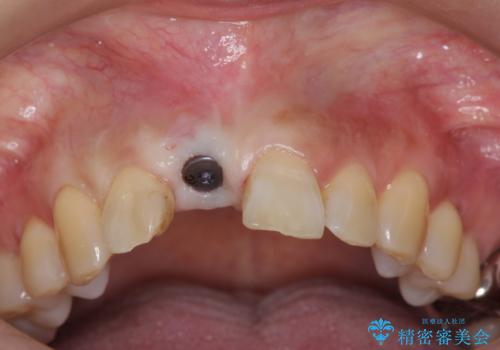

骨造成を伴う前歯のインプラント治療

- 前歯を外傷により失い、審美性の改善を求めて来院されました。

審美的・機能的に良好な位置に埋入するには、骨量が十分ではなかったため骨の造成を併用したインプラント埋入外科手術を行います。

前歯のインプラントを審美的に仕上げるには、インプラント周囲に十分な骨の量と厚みのある歯肉、そして埋入位置の精密な位置付けが重要です。